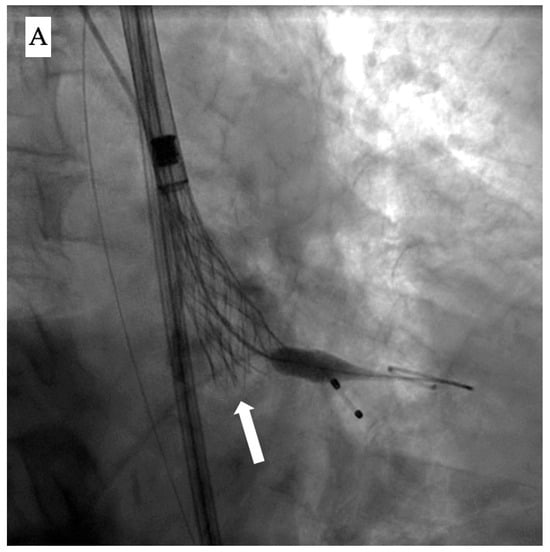

Once deployment has started, the two main fluoroscopic clues to identify it are (1) the appearance of a dense vertical line on the valve, reflecting the overlapping layers of the infolded stent cage, and (2) visual signs of underexpansion with a narrower-than-expected width [] (Figure 1A).

Figure 1.

Fluoroscopic and echocardiographic appearance of TAVI infolding. (A) Visual clues for recognizing this complication include a dense vertical line across the valve frame (white arrow) and the inability to reach the intended valve expansion. (B) Short axis window in echocardiography revealing the “Pac man” sign (white star).

Accordingly, evaluation of the bio-prosthesis in two orthogonal views or performing a c-arm fluoroscopic rotation is recommended to identify such complications. Infolding can also be confirmed by echocardiography through visualization of the “Pac-man” sign in the short axis view [] (Figure 1B).